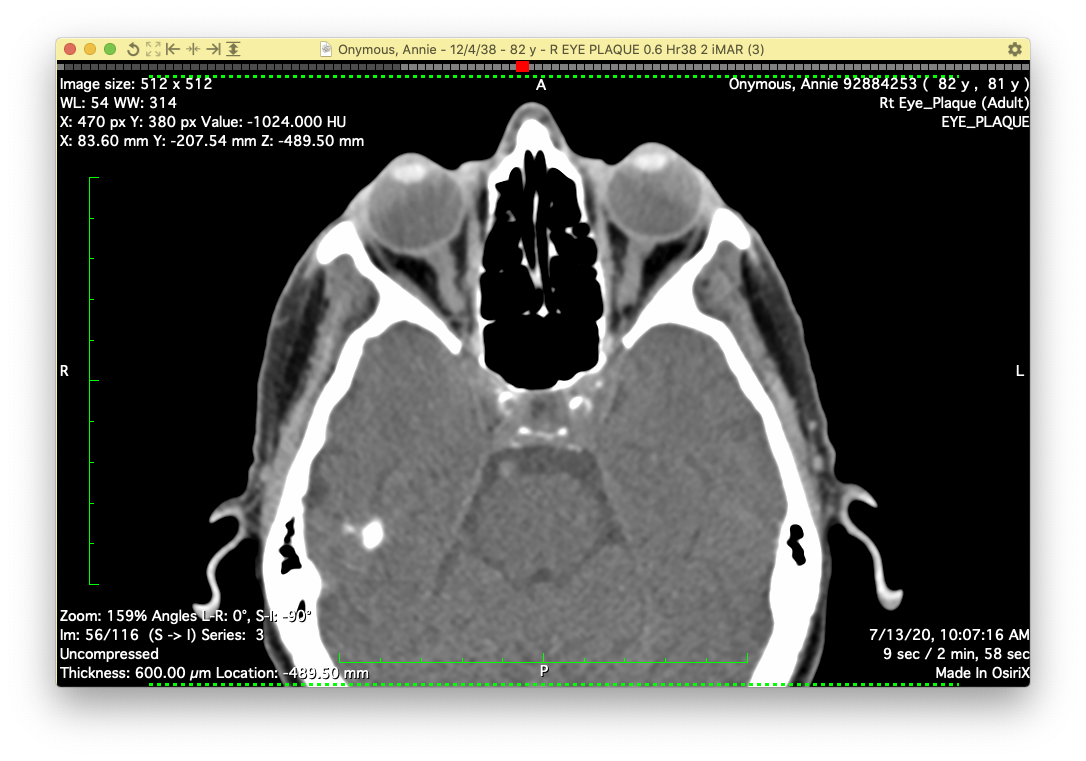

The imaging frame should include both eyes and extend at least a cm or two inferior and superior to the orbits.

AxialCT2

An axial imaging frame that includes the involved eye and at least half of the opposite eye is also acceptable as illustrated below.